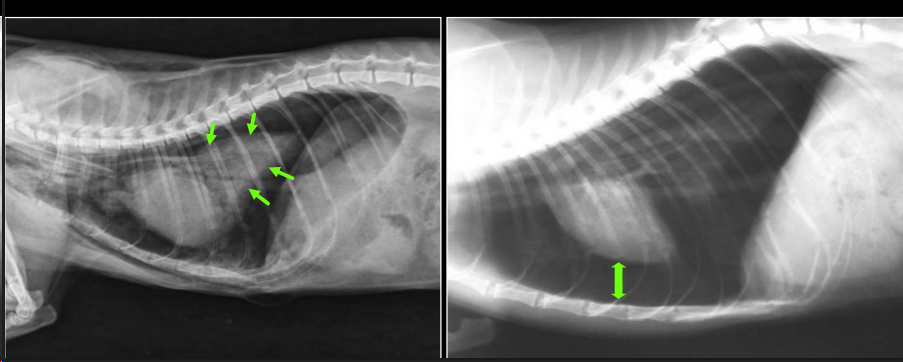

Neumotórax

Si hay un neumotorax y neuromediastino, el neumomediastino siempre es el causante

- Aire en cavidad pleural.

- RX:

- Desplazamiento dorsal del corazón (LL).

- Colapso pulmonar.

- Trama pulmonar no llega a pared torácica.

- Espacio radiolúcido entre pulmón y pared.

Cuando hay un neumotorax, al retraerse el pulmon se presentara un patron alveolar. Si el aire puede ir a ambos lados las presiones se compensan, anotensión. Si solo entra y no sale aumentara la presion y tendremos un neumotorax atensión